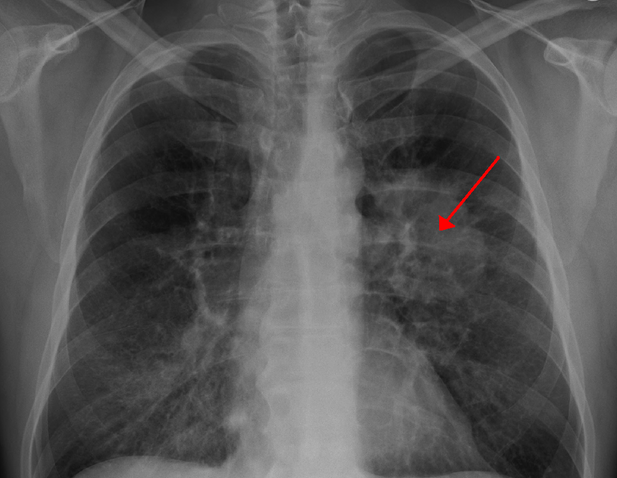

Je früher desto besser

Antonoff klärt es als "Es ist ein Missverständnis, dass ein Röntgenstrahl frühe Lungenkrebs fangen wird. Ein CT-Scan hat eine höhere Sensibilität, um frühzeitige Tumore oder vorkrebsartige Läsionen aufzudecken, und die Diagnose einer frühen Bühne bietet Ihnen den besten Schuss bei einer Heilung. Und denken Sie daran, dass ein klarer Scan nicht bedeutet, dass Sie das Rauchen beheben können. Jeden Tag, an dem Sie nicht rauchen, können Sie Ihr Risiko der Entwicklung von Lungenkrebs verringern. "

Älteste, ein leichtes Ziel?

Die meisten Lungenkrebspatienten leiden seit Jahren unwissentlich an der Krankheit, bevor er diagnostiziert wird. Nach Aufzeichnungen, im Jahr 2011, waren "82% der Patienten von Lungenkrebspatienten 60 Jahre alt oder älter. Bei den meisten Patienten, die mit Lungenkrebs diagnostiziert werden, werden mit einer Bühnen-III- iii- oder stufe-IV-Krankheit diagnostiziert. "

Gibt es keine Symptome?

Leider sind die Symptome von Lungenkrebs nicht sichtbar, bis er die fortgeschrittene Bühne erreicht hat. Ärzte suchen immer noch nach ähnlichen Merkmalen, die in den frühen Stadien häufiger sind. Nachfolgend werden die Symptome erwähnt, die er enthalten kann: